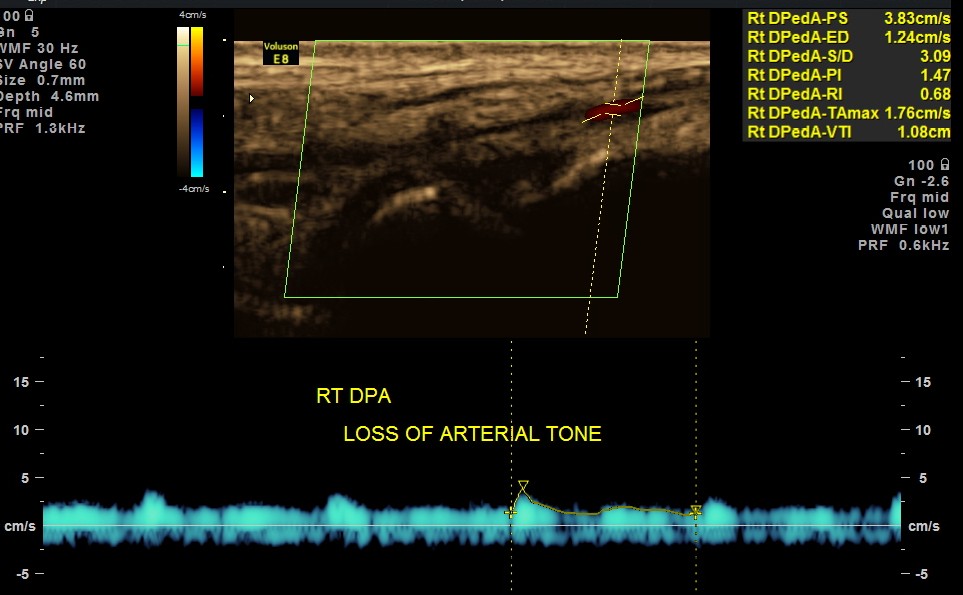

The following pictures were obtained .

BOTH DORSALIS PEDIS ARTERIES SHOW LOSS OF ARTERIAL TONE AND MONOPHASIC FLOW.

EXTENSIVE ATHEROSCLEROTIC OBSTRUCTIVE DISEASE OF THE LOWER LIMB ARTERIES WAS SEEN WITH THE CHANGES IN THE RIGHT COMMON FEMORAL ARTERY BEING MORE THAN THE LEFT CFA.